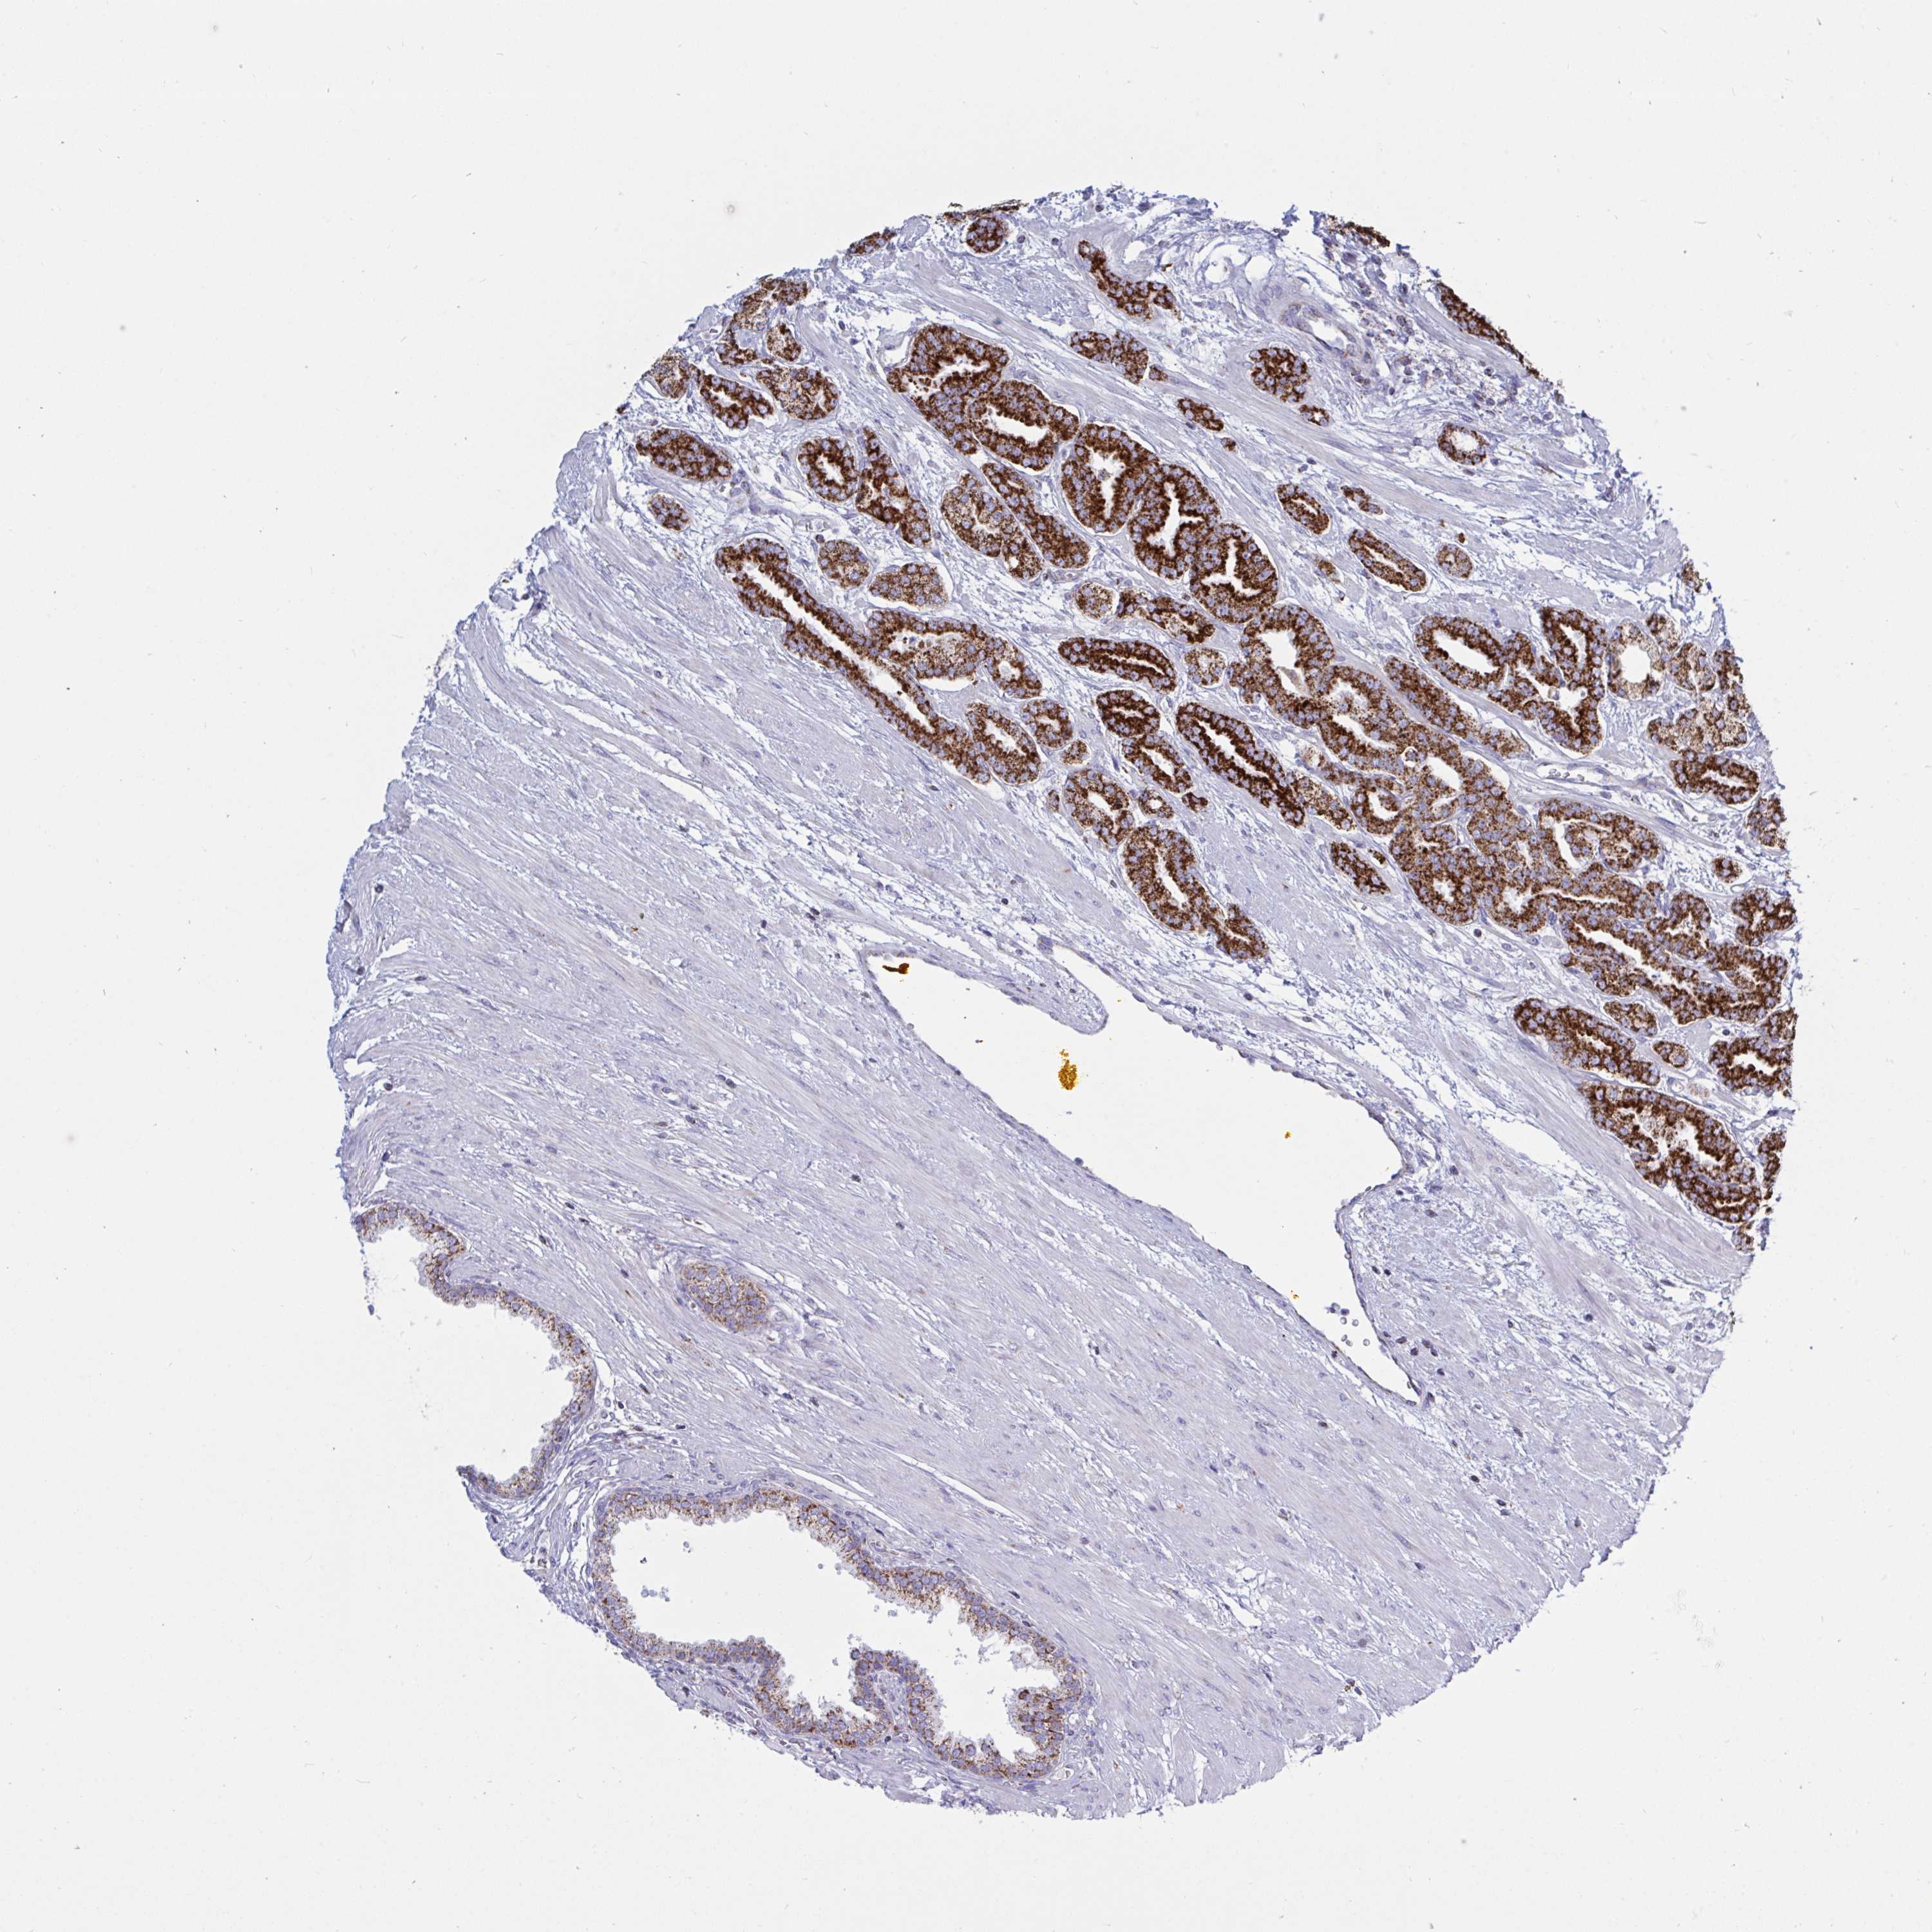

PROSTATE CANCER - Protein expressioni

A mouse-over function shows sample information and annotation data. Click on an image to view it in a full screen mode. Samples can be filtered based on level of antibody staining by selecting one or several of the following categories: high, medium, low and not detected. The assay and annotation is described here.

Note that samples used for immunohistochemistry by the Human Protein Atlas do not correspond to samples in the TCGA dataset.

Antibody stainingi

Antibody staining in the annotated cell types in the current human tissue is reported as not detected, low, medium, or high, based on conventional immunohistochemistry profiling in selected tissues. This score is based on the combination of the staining intensity and fraction of stained cells.

Each image is clickable and will lead to virtual microscopy that enables deeper exploration of all samples and also displays staining intensity scores, fraction scores and subcellular localization as well as patient and tissue information for each sample.

Antibody HPA038755

Antibody HPA048272

Antibody CAB017366

Staining

High

Medium

Low

Not detected

Intensity

Strong

Moderate

Weak

Negative

Quantity

>75%

75%-25%

<25%

None

Location

Nuclear

Cytoplasmic/membranous

Cytoplasmic/membranous,nuclear

Adenocarcinoma, NOS

Adenocarcinoma, High grade

Adenocarcinoma, Low grade